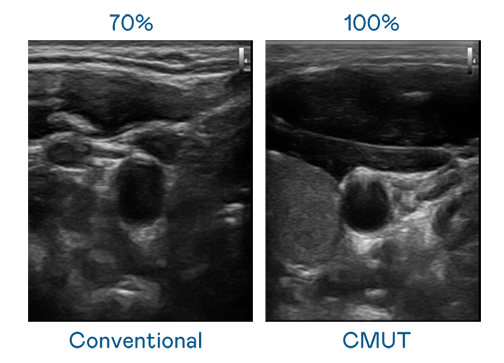

CMUT 技术是一种用电容式微机电元件来产生超音波讯号的技术。与传统 PZT 压电式技术相比,CMUT 频宽增加 30%,更宽频的超音波讯号让影像解析度大幅提升,是实现高影像品质医疗超音波扫描、促进精准医疗发展的关键技术。

大频宽带来超清晰影像

超音波影像的解析度高低,首先取决于探头能发出的讯号频宽。BBIN宝盈 CMUT 可提供高清晰的超音波讯号,提供高频宽、高灵敏度、影像纹理细节更高的超音波影像,协助医护人员缩短影像判读时间及利用精准的医疗影像进行诊断。